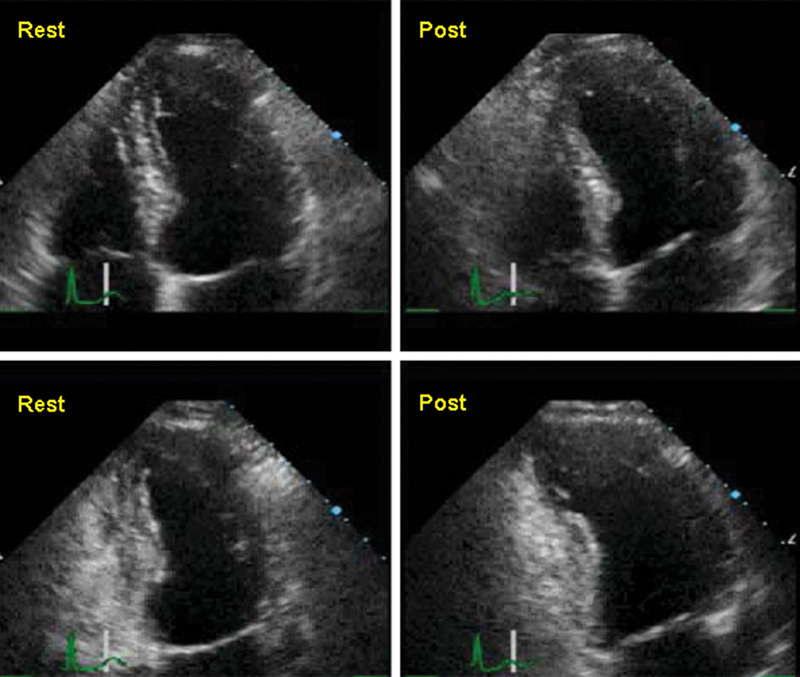

فحوصات تشخيصية لبعض امراض القلب والشرايين التاجية